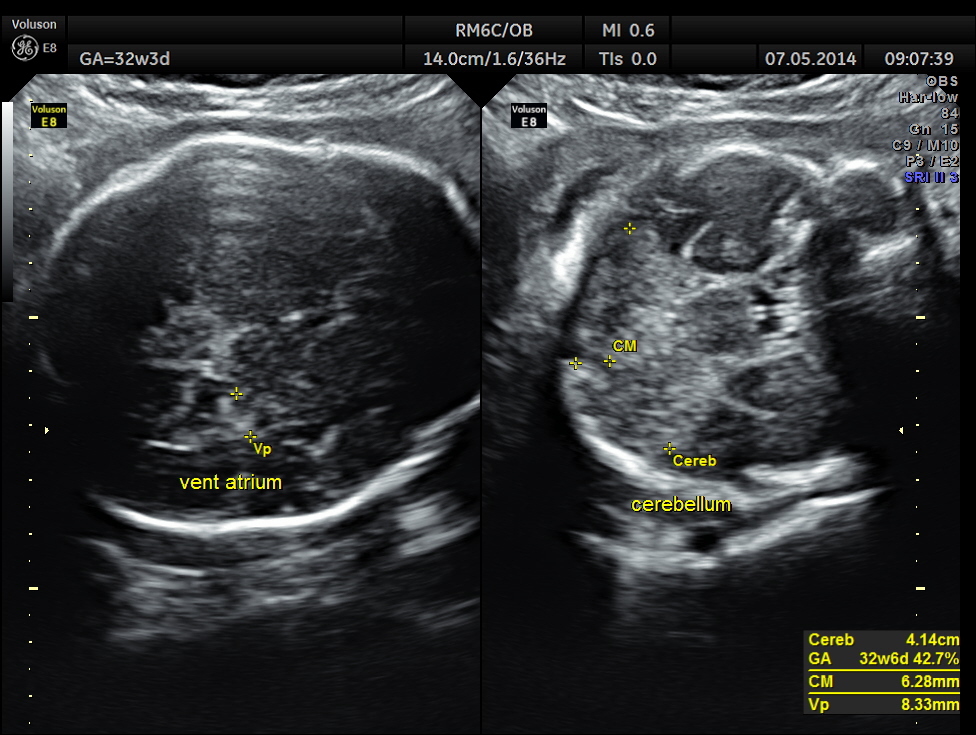

This was a 37 year old lady , a primi gravida referred for evaluation of intra uterine growth restriction. As per LMP the GA was 32 w 3 Days, but as per AUA the GA was 26 weeks . All the long bones were < 5.0 % tile. But cerebellum was 42.7 % tile. There was severe symmetrical growth restriction .